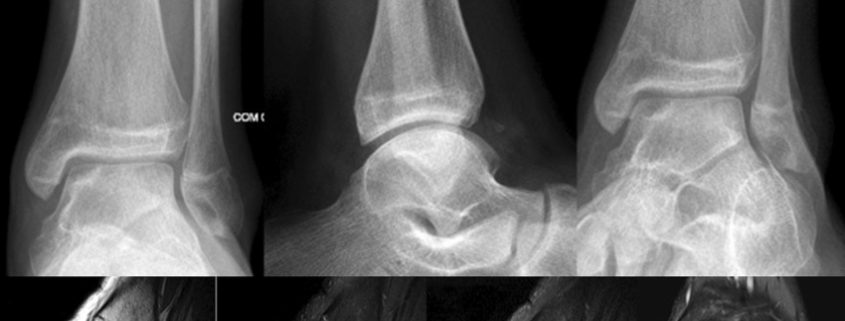

Diagnosis of ODT typically starts with a thorough physical examination by a healthcare professional. Your doctor will check your range of motion, level of discomfort, and signs of swelling. If ODT is suspected, imaging tests like X-rays, MRI, or CT scans may be ordered to confirm the diagnosis.